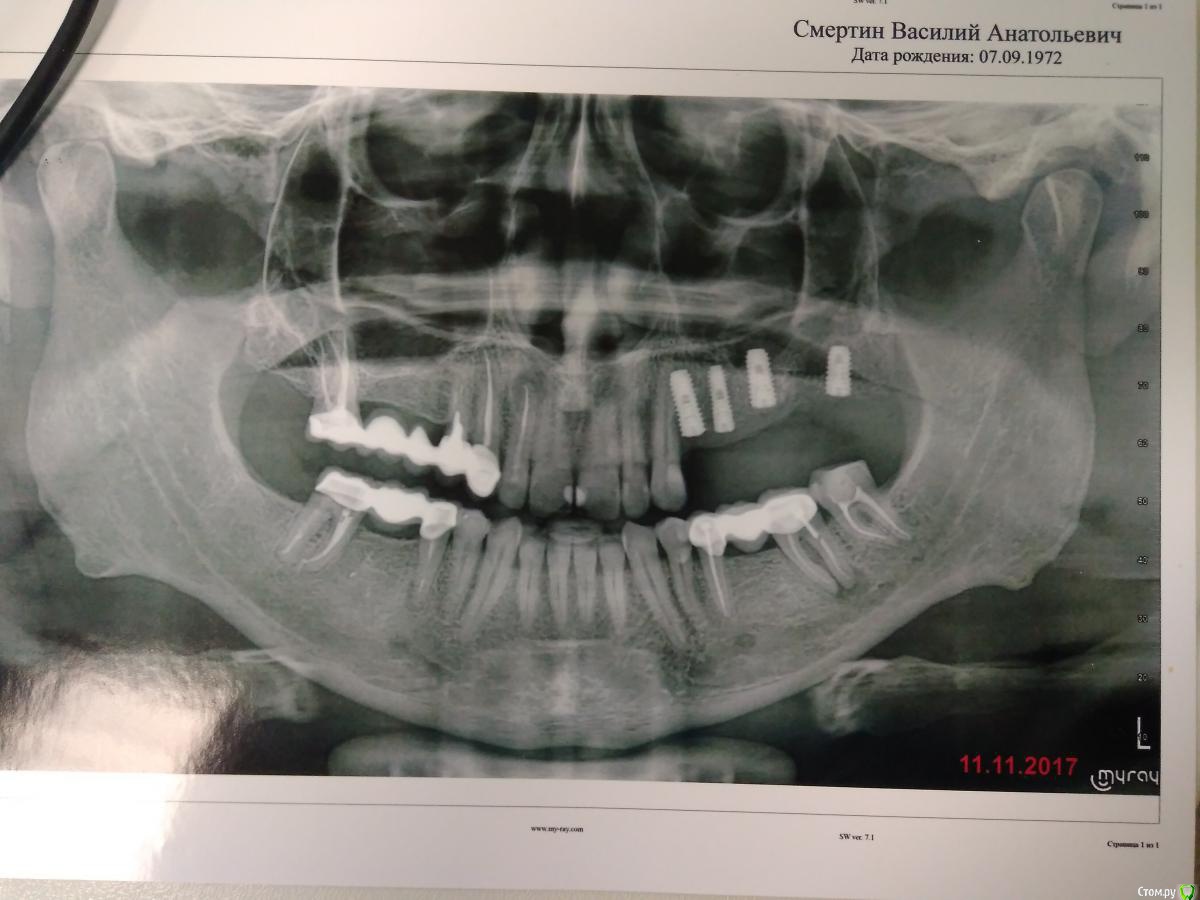

Smertofan Опубликовано 3 октября, 2018 Автор Поделиться Опубликовано 3 октября, 2018 Потому что при жевании твердой пищи появляется боль .Я почти уверен что,если бы инплантант былбы полностью в кости,то не болелобы Ссылка на комментарий

Evikrol Опубликовано 4 октября, 2018 Поделиться Опубликовано 4 октября, 2018 У вас под нижними коронками довольно таки большое воспаление, причём располагается рядом с нервом в результате боль может отражатся на верхнюю челюсть. Постучите по нижним коронкам. Ссылка на комментарий

Bier Опубликовано 5 октября, 2018 Поделиться Опубликовано 5 октября, 2018 Потому что при жевании твердой пищи появляется боль .Я почти уверен что,если бы инплантант былбы полностью в кости,то не болелобывы не правы. при нагрузке "работают" только первые 4мм имплантата. Ссылка на комментарий